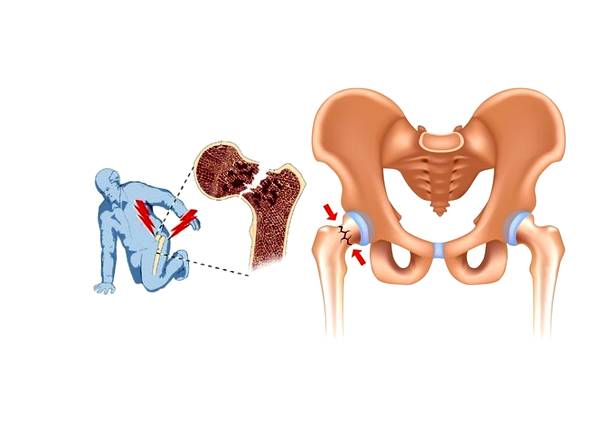

Las fracturas óseas pueden variar en gravedad, desde una simple fisura hasta una rotura completa en varias partes. El tipo de fractura influye en las opciones de tratamiento. Las fracturas capilares o por estrés son pequeñas fisuras difíciles de detectar, mientras que las fracturas completas rompen el hueso en dos partes. Las fracturas abiertas implican que el hueso atraviesa la piel, y las fracturas conminutas significan que el hueso se ha fragmentado en múltiples piezas.

Una fractura ósea es evidente si el hueso sobresale a través de la piel, pero en otros casos, puede ser menos obvio. Los síntomas incluyen dolor intenso, hinchazón, moretones, dificultad para mover o soportar peso en la extremidad, y en algunos casos, deformidad o un ángulo anormal de la extremidad.

El objetivo del tratamiento de las fracturas es permitir que el hueso sane y se fusione de nuevo. A menudo, esto puede lograrse inmovilizando el hueso durante varios meses con la ayuda de una escayola y una férula. Cuanto más grave es la fractura, más probable es que se recomiende la cirugía.

Por ejemplo, una fractura abierta o conminuta requerirá una intervención quirúrgica para garantizar que el hueso vuelva a crecer por completo y soporte su peso con seguridad. La reparación quirúrgica implica el uso de varillas, tornillos o placas metálicas para fijar el hueso en su sitio o alinearlo mientras se cura.